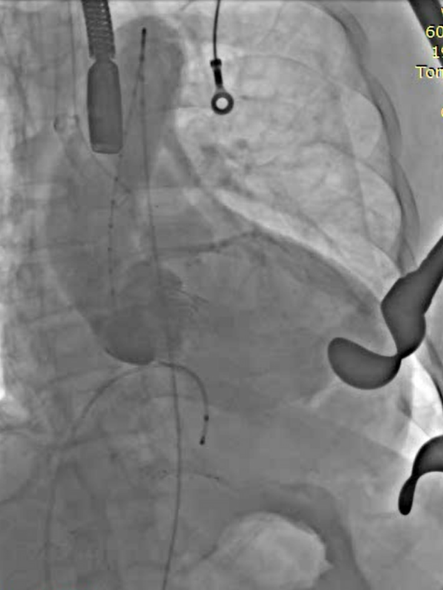

植入器进入升主动脉

定位件入窦

瓣膜落座瓣环平面

全麻后取仰卧位,消毒。取左前胸第5肋间切口进胸,腔镜辅助下游离左侧乳内动脉(LIMA)备用。肝素化。显露左前降支动脉(LAD),于其狭窄远段切开,将LIMA与之端侧吻合。血管桥排气后开放,测桥血流量满意。经股静脉植入心脏临时起搏器并确认正常工作。经股动脉置入造影导管至升主动脉根部,造影显示主动脉瓣大量反流,窦部结构可。3-0 Porlene线带毛毡片做荷包,经单弯导管引导超滑导丝至降主动脉,更换加硬导丝,导丝尖端于髂动脉分叉处。置入带主动脉瓣输送系统,造影定位下,准确释放29# J-Valve至主动脉瓣瓣环处,造影显示左右冠脉血流正常,TEE证实瓣膜位置可,未见明显反流。撤出输送系统,收紧荷包并缝合止血。放置胸管,逐层关闭各切口。